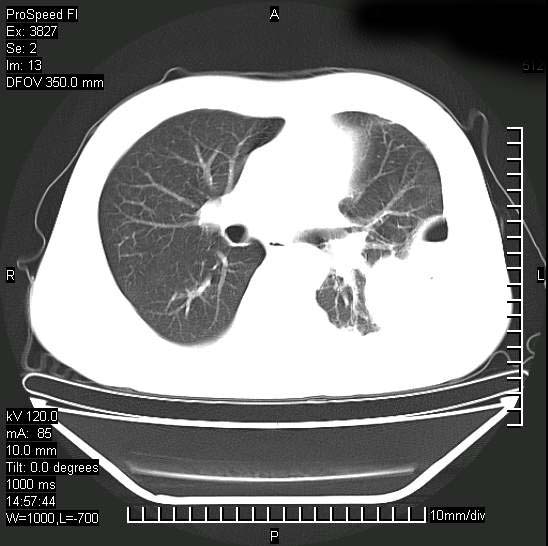

男性,一月前出现右侧肋区疼痛,较剧烈,干咳,无发热,自诉使用抗炎药后缓解,几天前又出现左侧剧烈疼痛,

发热,体温38。9,今天ct,考虑左侧包裹性脓胸,胸腔积液,右上中肺小斑片影,结核/炎症?胸水未见恶性细胞。